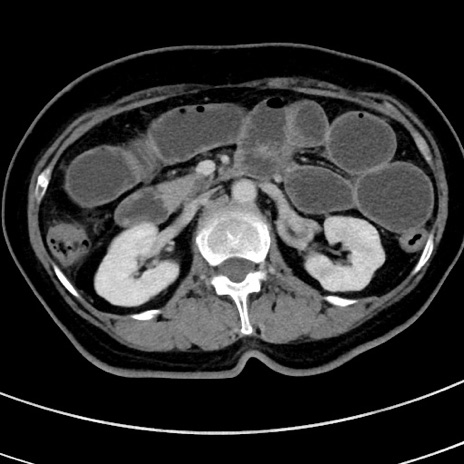

症例9(横断像)

【症例】 60歳代女性

【主訴】むかつき、みぞおちの痛み

【現病歴】3日前よりむかつきがあり、食事がとれない。

【既往歴】糖尿病

【身体所見】発熱なし、心窩部圧痛軽度あるも、腹膜刺激症状なし。

【データ】WBC 7400、CRP 1.92